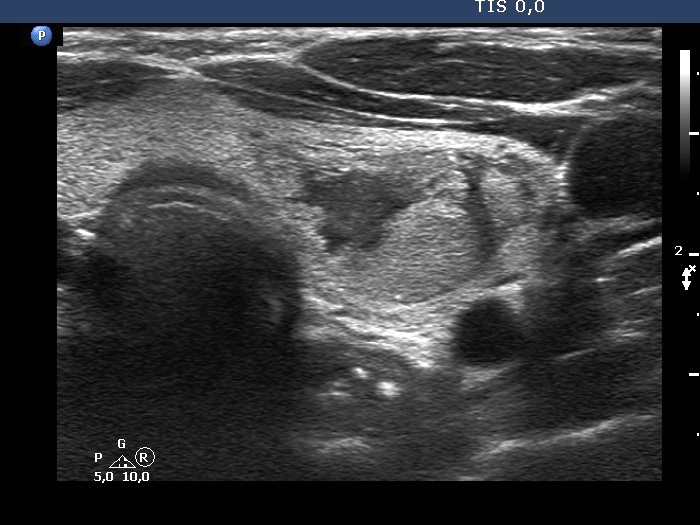

Second examination 4 years later (second and third rows of images):

Ultrasonography. The cystic nodule had refilled. The presentation remained the same.Seven mL brown fluid was aspirated. Cytology: benign, cystic lesion.